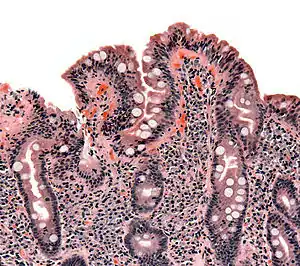

Elle met en évidence une atrophie villositaire associée à une augmentation des lymphocytes intraépithéliaux, une hypertrophie des cryptes et une infiltration plasmolymphocytaire du chorion. Ces lésions sont évaluées selon la classification de Marsh, allant de I (simple augmentation isolée des lymphocytes intraépithéliaux) à IIIc (atrophie villositaire sévère)[53].